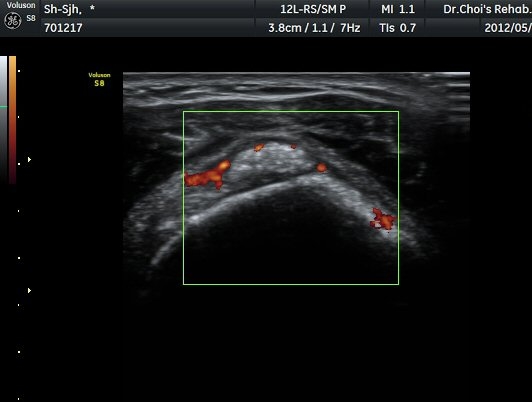

µÈ´Ù(»çÁø 3). ±Ø»ó°Ç Á¾´Ü¸é°Ë»ç»ó ±Ø»ó°Ç ºÎÂøºÎ¿¡ °í¿¡ÄÚ µ¢¾î¸®°¡ °üÂûµÇ°í(»çÁø 4, 5)

ÆÄ¿öµµÇ÷¯ °Ë»ç¿¡¼­ Ç÷·ùÁõ°¡¸¦ º¸ÀδÙ(»çÁø 6).  Ⱦ´Ü¸é°Ë»ç¿¡¼­µµ °í¿¡ÄÚ µ¢¾î¸®¿Í

Ç÷·ùÁõ°¡°¡ È®ÀεȴÙ(»çÁø 7, 8).